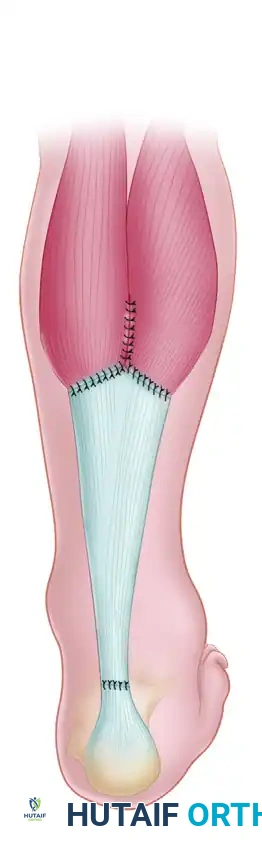

Advancement and Y-Repair: The aponeurotic flap is advanced distally, bridging the defect. The proximal "V" defect is then closed in a "Y" configuration. The advanced distal end of the flap is anastomosed end-to-end with the distal Achilles stump using heavy, non-absorbable core sutures (e.g., Krackow technique).

- Weaving: Pass the FHL tendon through the tunnel, then route it proximally. Weave the FHL tendon from distal to proximal through the remaining substance of the Achilles tendon (or the aponeurosis) using a tendon weaver. Continue weaving until the full length of the harvested FHL tendon is utilized.

- Securing the Construct: Secure the weave at multiple points using heavy, non-absorbable sutures (e.g., 1-0 Dacron or FiberWire).

- Supplementation (Optional): If the repair requires additional bulk, it can be supplemented using the plantaris tendon or a central turndown slip of the proximal Achilles tendon.

Phase 5: Closure

- Paratenon Closure: Meticulously close the paratenon over the repair using absorbable sutures (e.g., 2-0 or 3-0 Vicryl). This layer is vital for preventing adhesions and providing vascularity.